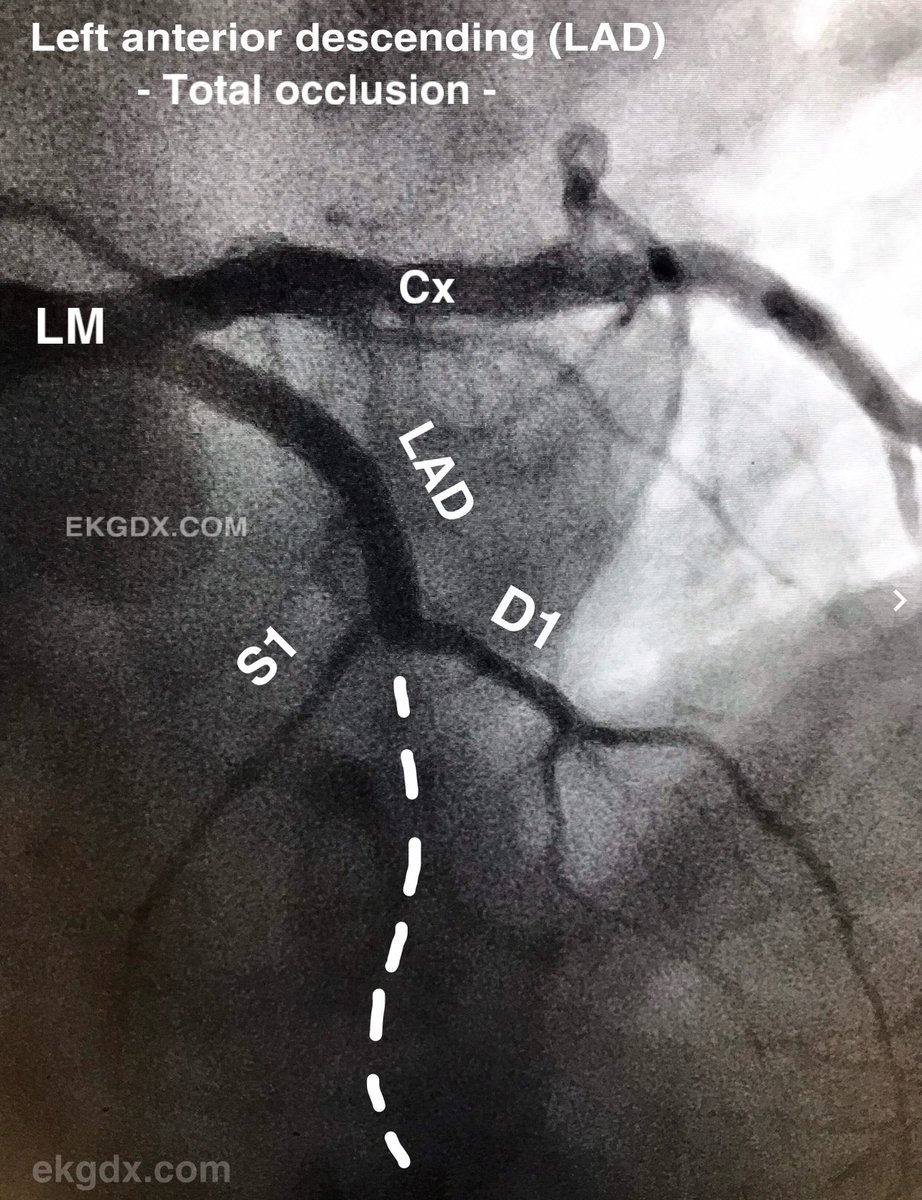

1/ Today's 🧵 is about the de #Winter pattern.

@ekgdx Image 2/  The de Winter pattern holds significance as it is linked to the occlusion of the proximal left anterior descending coronary artery (LAD) when identified in the electrocardiogram (ECG) of individuals experiencing chest pain or displaying a history suggestive of acute coronary syndrome. In fact, this pattern is present in approximately 2% of patients diagnosed with proximal occlusion of the LAD.